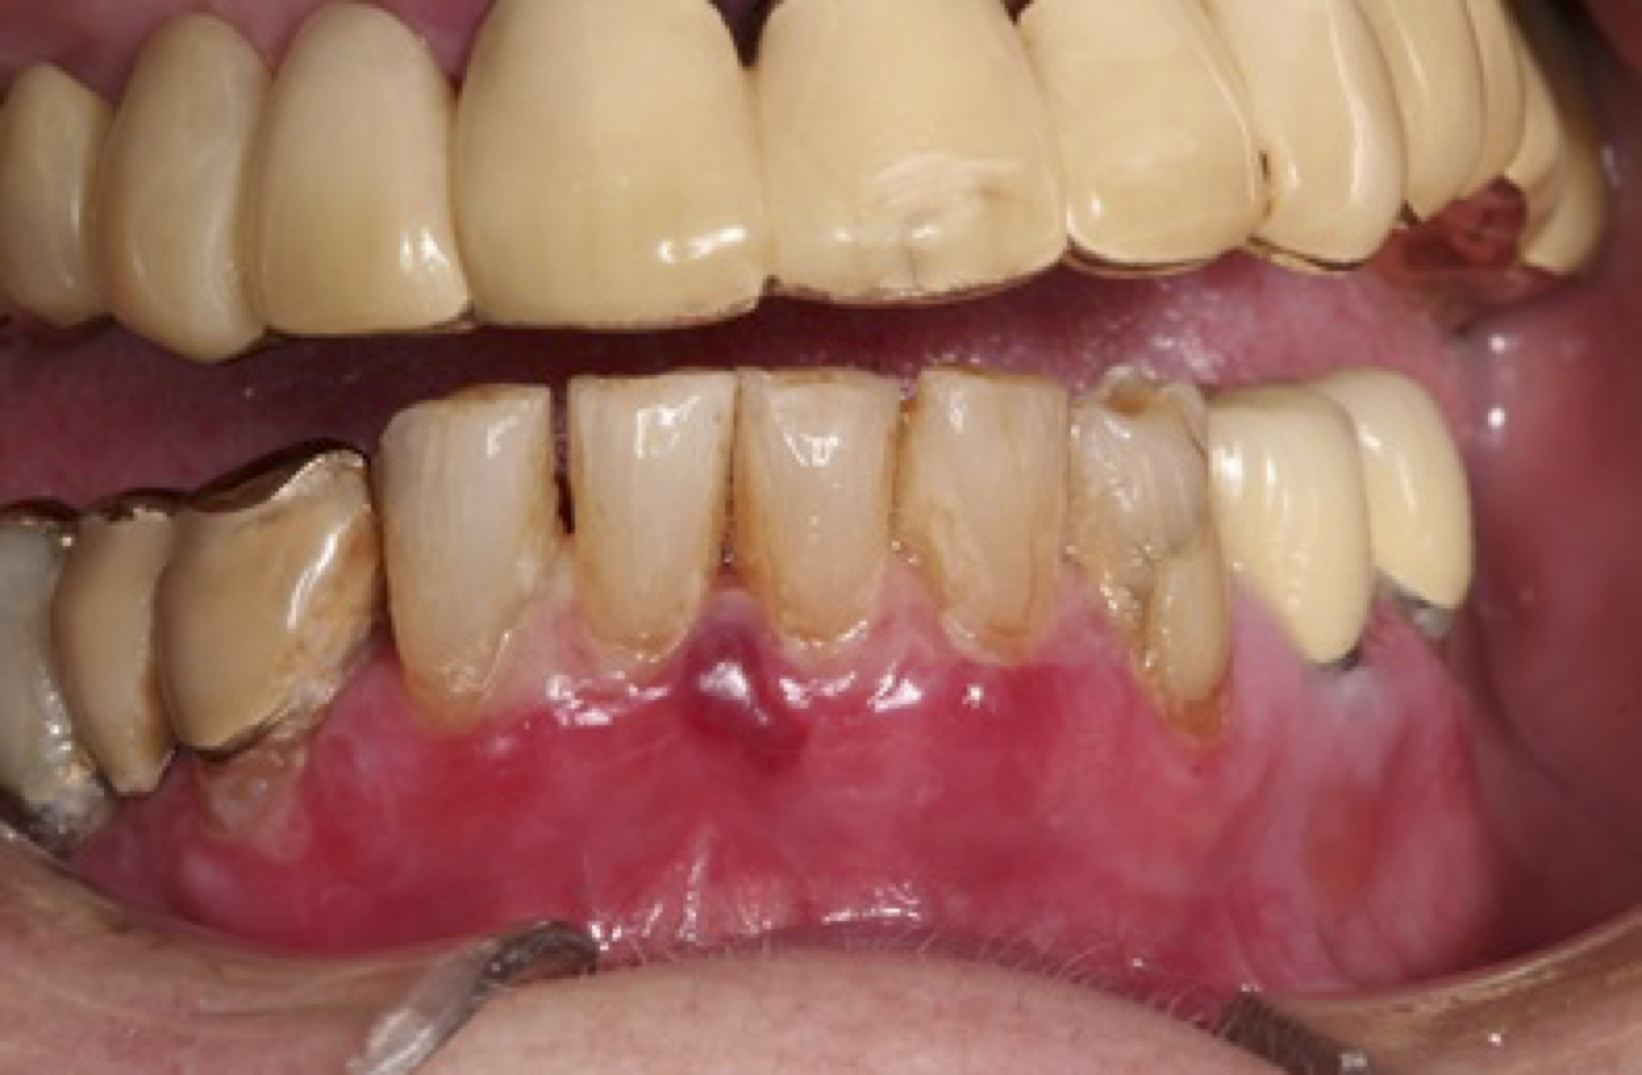

Pemfigoid är en heterogen grupp av kroniska, autoimmuna sjukdomar som ger symtom i form av blåsor/ulcerationer på hud och slemhinnor. Pemfigoid medför risk för stort lidande och ofta en lång behandling med flera biverkningar. Det är framförallt äldre personer som drabbas och incidensen har ökat de senaste åren.

- Slemhinnepemfigoid (eng. Mucous membrane pemphigoid – MMP). Munslemhinnan är den vanligaste lokalisationen (ca 85% av patienterna) och näst därefter drabbas ögonslemhinnan-konjunktivan (ca 65%). Även andra slemhinnor i nasopharynx, esophagus, larynx och på genitalia kan vara involverade, liksom huden.